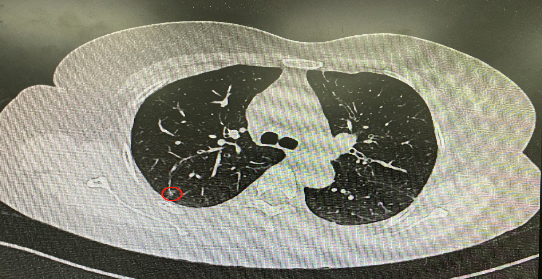

今年54歲的李女士(化名)7月初突然出現(xiàn)右上部腹痛,起初并未在意,以為稍作休息就會(huì)好轉(zhuǎn),但疼痛卻并未消退,持續(xù)了一個(gè)星期。李女士實(shí)在難以忍受,才在家人陪伴下來到西安國際醫(yī)學(xué)中心醫(yī)院就診。胸外科二病區(qū)崔凱主任接診患者后,詳細(xì)詢問病情并查閱檢查資料,經(jīng)胸部HRCT檢查,結(jié)果提示:右肺上葉后段混合密度結(jié)節(jié)影,考慮原位癌可能,即將患者收入胸腔外科二病區(qū)住院治療。

經(jīng)與患者家屬溝通,崔凱主任決定行外科手術(shù)治療。為達(dá)到精準(zhǔn)切除,術(shù)前需進(jìn)行肺小結(jié)節(jié)切除前定位。由于結(jié)節(jié)位于右肺上葉后段,傳統(tǒng)經(jīng)胸外穿刺術(shù)無法抵達(dá)病灶。崔凱主任與呼吸內(nèi)科一病區(qū)歐陽海峰主任討論后,決定擬行LungPro全肺診療導(dǎo)航下染色定位。即術(shù)前通過Lung Pro導(dǎo)航規(guī)劃染色位置,經(jīng)Lung Pro實(shí)時(shí)引導(dǎo)支氣管鏡抵達(dá)既定位置,注入亞甲藍(lán)染色劑標(biāo)記結(jié)節(jié)位置。

使用術(shù)前規(guī)劃系統(tǒng)重建全肺3D模型,并于外科醫(yī)生討論染色位置,最終確定標(biāo)記染色點(diǎn)—右肺上葉后段b亞段(RB2b)。術(shù)中使用P290(4.9mm外徑)標(biāo)準(zhǔn)支氣管鏡,根據(jù)導(dǎo)航術(shù)前規(guī)劃路徑,Lung Pro實(shí)時(shí)導(dǎo)航下,GS鞘管進(jìn)入RB2b遠(yuǎn)端官腔外病灶并注射亞甲藍(lán)染色劑。